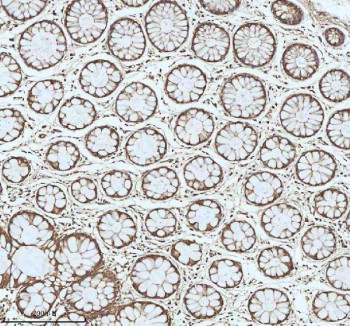

Adding 0.2 ml of distilled water will yield a concentration of 500 ug/ml. MYH14 antibody detects Myosin-14, encoded by the MYH14 gene on chromosome 19q13.33. MYH14 antibody is used in studies of cytoskeletal regulation, hearing, and cellular motility. Myosin-14 belongs to the class II non-muscle myosins, functioning as an actin-based motor protein. It regulates actin filament organization, adhesion, and vesicle trafficking. Expression is widespread, with high levels in inner ear hair cells, smooth muscle, and neuronal tissue, where it supports specialized mechanical and sensory functions.Structurally, Myosin-14 is a large protein containing an N-terminal motor domain with ATPase activity, a neck region with IQ motifs that bind light chains, and a coiled-coil tail that mediates dimerization and filament assembly. Its motor domain hydrolyzes ATP to generate force for actin filament sliding, supporting contractility and cytoskeletal rearrangements. Isoforms derived from alternative splicing confer tissue-specific functions.Functionally, Myosin-14 regulates actin cytoskeleton dynamics, contributing to cell migration, adhesion, and intracellular transport. In neurons, it supports axon guidance and synaptic function. In the inner ear, Myosin-14 is essential for mechanotransduction and hearing. Knockout or mutation of MYH14 disrupts hair cell function, leading to progressive hearing loss. Researchers use MYH14 antibody to investigate cytoskeletal biology, neuronal function, and auditory physiology.Clinically, MYH14 mutations are associated with autosomal dominant non-syndromic hearing loss (DFNA4A). Mutations disrupt motor activity or actin binding, impairing hair cell function. Myosin-14 variants are also linked to peripheral neuropathy and craniofacial developmental disorders. Altered expression of MYH14 has been observed in cancers, where cytoskeletal regulation influences invasion and metastasis. NSJ Bioreagents offers MYH14 antibody as a tool for studies of cytoskeletal regulation, auditory biology, and disease mechanisms.Experimentally, MYH14 antibody is used in western blotting to detect the ~230 kDa protein, in immunofluorescence microscopy to visualize actin-associated localization, and in immunohistochemistry to study hair cell and neuronal expression. Co-immunoprecipitation with MYH14 antibody isolates complexes of actin, myosin light chains, and regulatory proteins.

| Application: | WB, IHC, FC, ELISA |